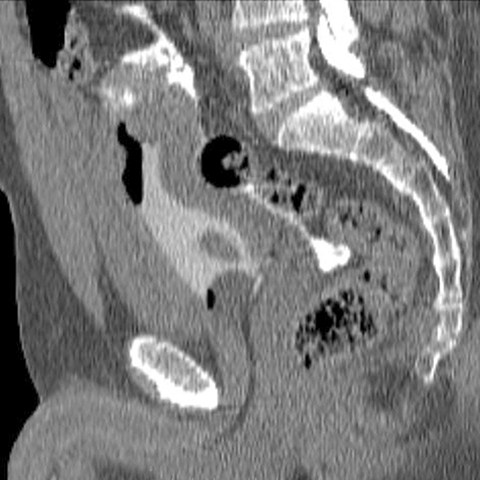

Intraperitoneal rupture of bladder, CT (sagittal) [2 of 2]